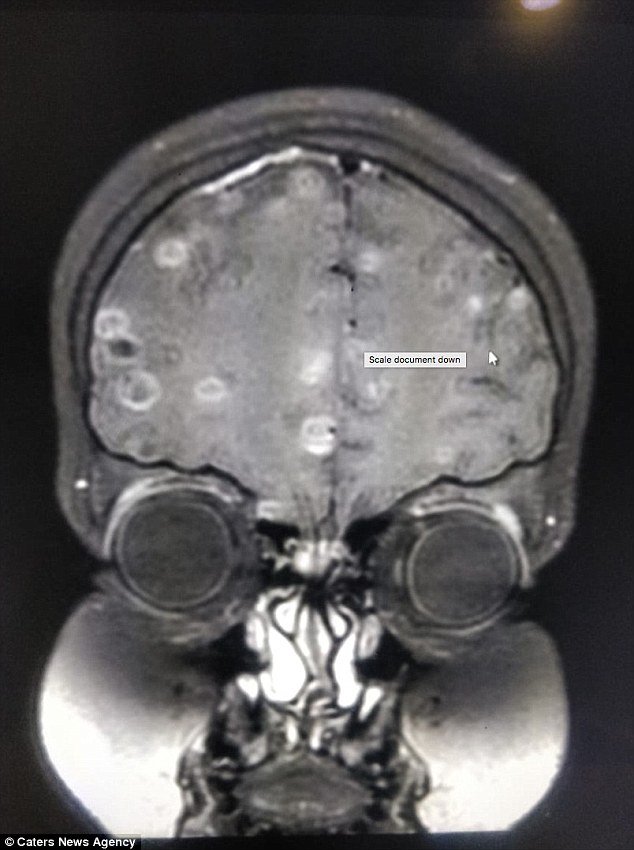

Ở đó, sau những lần chụp cắt lớp não bộ, cô bé được chẩn đoán là mắc chứng loạn thần kinh. Nguyên nhân chính là cô bé bị nhiễm sán dây nặng, trứng của chúng đi vào mạch máu từ dạ dày lên đến não và làm tổ ở đó. Lý giải cho nguyên nhân nhiễm sán dây, các bác sĩ cho biết, cô bé đã ăn trái cây chưa được rửa sạch và thịt chưa được nấu kỹ.

Praveen Gupta, giám đốc thần kinh tại Bệnh viện Fortis, cho biết: “Việc chụp cắt lớp phần não của cô bé đã cho thấy hơn 100 chấm trắng hình thành do trứng của sán dây. Việc cơ thể bị xuất hiện các triệu chứng sưng tấy và nhiễm trùng chính là do ăn phải thực phẩm có chứa trứng sán.

Khi trứng xâm nhập não bộ qua hệ thần kinh, chúng gây ra chứng loạn thần kinh, biểu hiện thông qua những cơn đau đầu dữ dội, những cơn co giật và tâm lý bất ổn. Có thể nhiều người không biết, nhưng hiện tượng trứng sán dây phá hoại chức năng não bộ là rất phổ biến”.